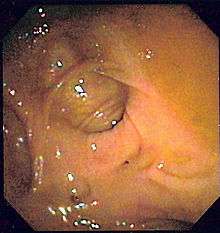

Colonoscopy

Colonoscopy is the test of choice in the majority of patients with acute Lower GI bleeding as it can be both diagnostic and therapeutic. The diagnostic accuracy of colonoscopy in lower GI bleeding ranges from 48% to 90%, and urgent colonoscopy appears to increase diagnostic yield. This wide range in yield is partially explained by different criteria for diagnosis, as often if no active bleeding, nonbleeding visible vessel, or adherent clot is found, bleeding is attributed to a lesion if blood is present in the area. The presence of fresh blood in the terminal ileum is presumed to indicate a non colonic source of bleeding. The overall complication rate of colonoscopy in acute lower GI bleeding is 1.3%. Bowel preparation is safe and well-tolerated in most patients. The complication rate of colonoscopy in an unprepped colon may be higher. About 2–6% of colonoscopy preparations in acute lower GI bleeding are poor. Between 4 and 8 L of Golytely should be administered orally or via nasogastric tube until the effluence is clear.[8]